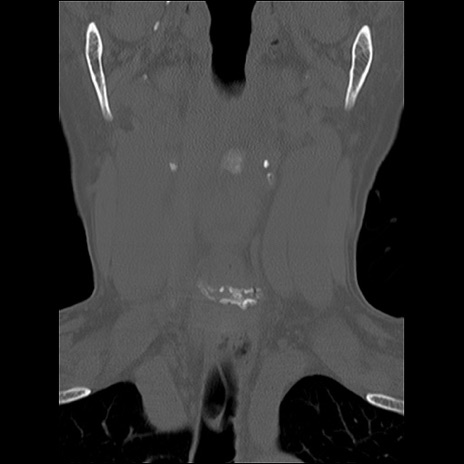

症例48 頚椎CT(冠状断像)

頚椎CT